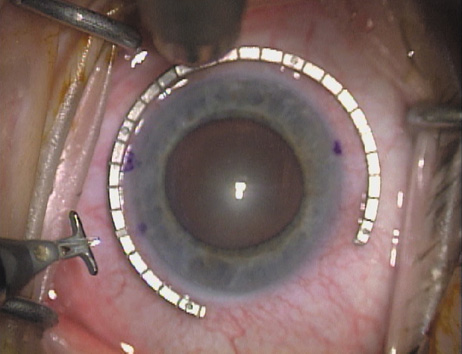

Case 1 is a 68-year-old male who presented for right cataract surgery. His refraction was −1.00 +2.25 × 80 and was recorded as reliable, consistent with his modest cataract density. Keratometry readings were 44.75 × 75 and 43.00 × 165. Corneal topography confirmed slightly more than 2.00 D of regular and slightly oblique cylinder. Consulting the nomogram, a plan was devised for a pair of LRIs to be centered over the 75-degree axis, with each incision delineating 45 degrees of arc. A single plane phaco incision was used and maintained at a size of less than 3.2 mm (Figs. 811).

Fig. 9. The broad hash marks of the fixation ring/gauge are centered over the 75-degree meridian, using the 6:00 limbal mark for orientation. Alternatively, a Mendez gauge may be used. (Reprinted from Hardten DR, Lindstrom RL, Davis EA. Phakic Intraocular Lenses: Principles and Practice. Thorofare, NJ: SLACK Incorporated, 2004, with permission.)